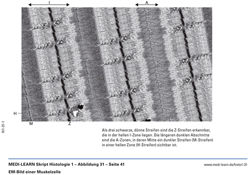

EM-Bild einer Muskelzelle